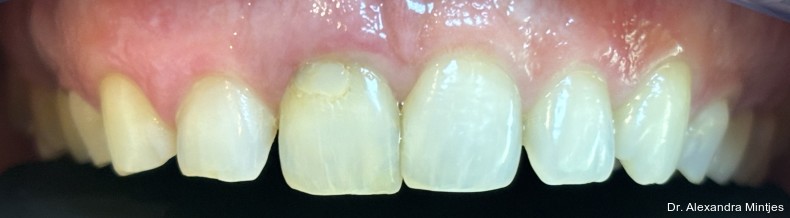

Bei der Erstvorstellung zeigte die vorhandene Füllung einen deutlichen Randspalt, war verfärbt und nach apikal hin insuffizient. Klinisch präsentierte sich ein dicker gingivaler Phänotyp mit ­harmonischer Weichgewebsbalance, jedoch bestand distal eine lokalisierte, entzündliche Zahnfleischtasche (Abb. 1). Es war zu vermuten, dass das nekrotische bzw. resorptive Hartgewebe nicht vollständig entfernt worden war. Auf dem DVT wurde das Ausmaß des Defekts deutlich. Zu­dem ließ sich eine deutliche apikale Aufhel­lung nachweisen, die Patientin war jedoch beschwerdefrei (Abb. 2).